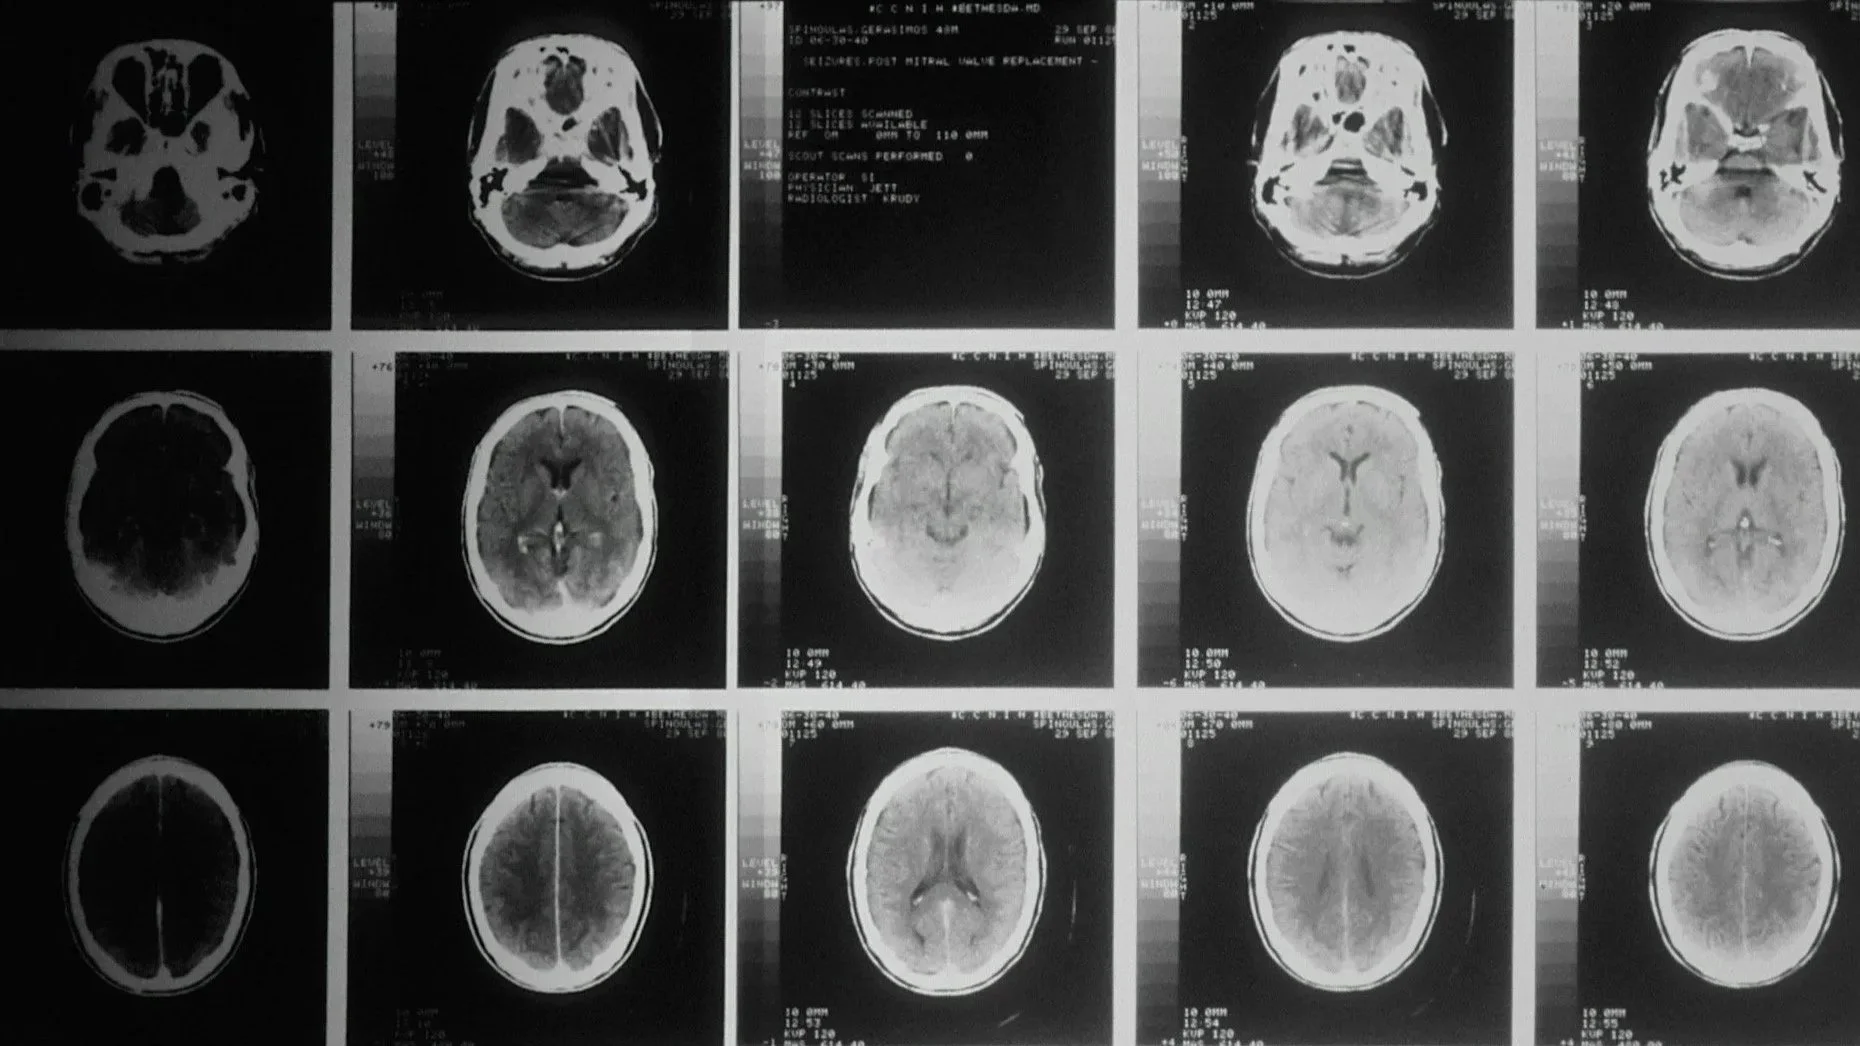

Brain imaging studies have shown changes in activation patterns following EMDR treatment, including reduced activity in threat-detecting regions and increased engagement in areas that involve regulating and meaning-making. This reflects neuroplastic change: the brain is updating how it stores and responds to the experience.